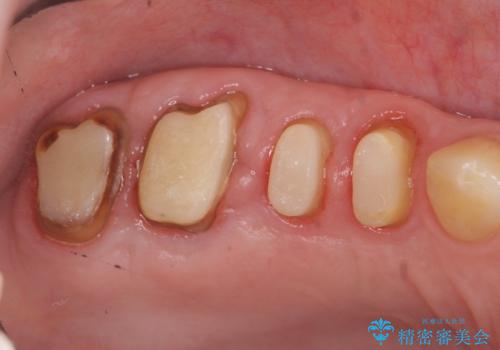

クラウンの製作スペースの付属 →歯周外科によるスペースの確保

機能の回復・再感染の予防 →精密なジルコニアクラウンの作製